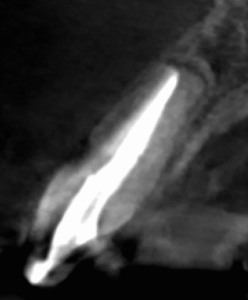

PA(2025.10.22)

CBCT(2025.10.22)